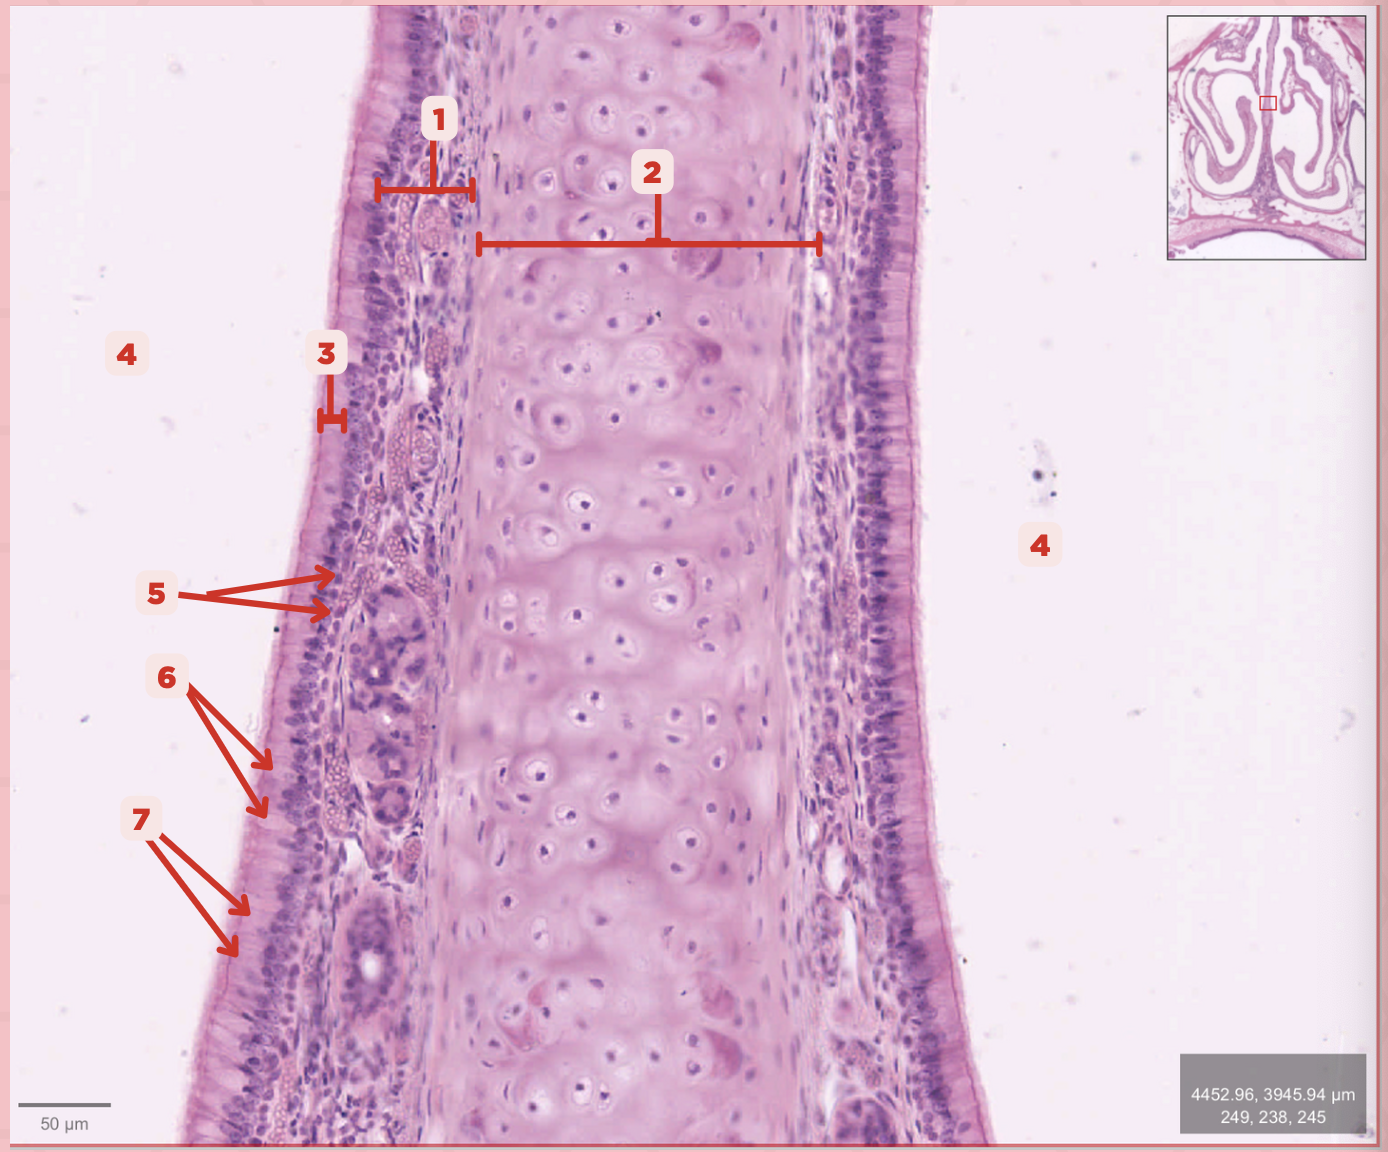

Identify the structure labeled as 1.

Hyaline Cartilage

Identify the structure labeled as 2.

Respiratory Epithelium

Identify the structure labeled as 3.

Nasal Cavity

Identify the structure labeled as 4.

Basal Cells

Identify the structure labeled as 5.

Goblet Cells

Identify the structure labeled as 6.

Ciliated Columnar Cells

Identify the structure labeled as 7.

Adipose tissue

What type of tissue is sometimes seen between the bony spicules?

Serous and Mucous Glands

What glands are present in the Lamina Propria?